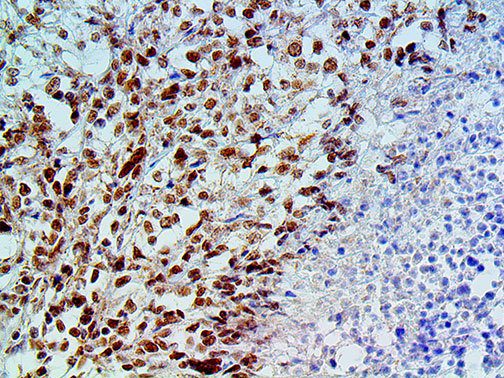

The first cytokines released are interleukin 1β (IL-1β) and tumor necrosis factor-α (TNF-α), which attract a variety of circulating white blood cells (WBCs) to the infection site, including neutrophils, monocytes, macrophages, and natural killer (NK) cells. This response, along with the antipathogenic chemicals released by these cells (i.e., complement), comprise the innate immune response. These cells directly attack the invading pathogen and also release additional cytokines, chief among them interleukin-1 and 6 (IL-6). IL-6 is essential for invoking the adaptive immune response, which calls T-cells, B-cells, and T helper (Th) cells to the infection site. IL-6 also stimulates further recruitment, proliferation and activation of macrophages.

It is the ICU physician who is most likely to witness one of the deadliest manifestations of the abnormal immunological response, the cytokine storm syndrome (CSS). This response is also referred to by some as the cytokine release syndrome (CRS). CSS is characterized by continuous activation and expansion of macrophage and lymphocyte populations, which secrete large amounts of cytokines, causing the cytokine storm. This massive cytokine release is akin to hemophagocytic lymphohistiocytosis (HLH) disease, a syndrome characterized by initial unchecked and persistent activation of cytotoxic T lymphocytes and NK cells.